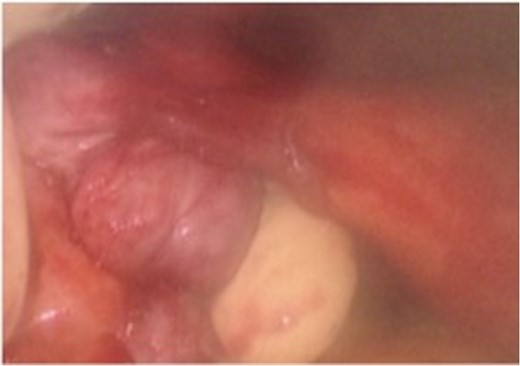

Two weeks later the patient was taken to the operating room for a hand-assisted laparoscopic colon resection and left oophorectomy. Intraoperatively, there were adhesions between the sigmoid colon and left anterolateral pelvic sidewall. Figure 3 shows the inflamed left ovary and fallopian tube adjacent to the sigmoid colon. The left ovary and a small portion of the left fallopian tube were dissected, and then resected en bloc with the sigmoid colon. Figure 4 depicts the uterus status post-resection. An end-to-end anastomosis was performed to the inraperitoneal rectum. The patient had an uncomplicated hospital course and was discharged home on post-operative Day number 2. One month later, the patient was doing well with normal bowel function, resolution of her UTI’s and resolved abdominal pain.

Intra-operative findings of the colo-ovarian fistula including grossly inflamed left ovary and fallopian tube.